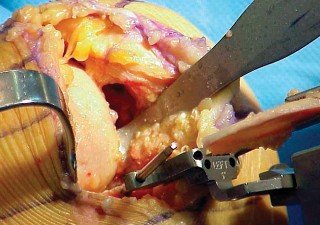

2. الوضع الجراحي والتعرض

- الوضع: يُوضع المريض في وضع الاستلقاء (Supine positioning) مع وضع كيس رمل أسفل الركبة أو حامل للساق يسمح بثني وفرد الركبة. يجب أن يكون الوضع مماثلاً لوضع جراحة TKA، مع استعداد لتحويل الإجراء إلى TKA إذا لزم الأمر.

- العاصبة (Tourniquet): تُستخدم عاصبة وتُوضع في أعلى الفخذ لتقليل النزيف.

-

الشق الجراحي:

يُستخدم شق طولي في الجانب الإنسي (الداخلي) من الركبة. يجب أن يكون الشق كبيرًا بما يكفي لتوفير رؤية جيدة للمفصل الرضفي الفخذي وإمكانية التحويل إلى TKA.

- فتح المفصل (Arthrotomy): يكون الفتح خطيًا وموازياً لألياف الوتر الرضفي، ويمتد إلى عظم الظنبوب وإلى الجزء السفلي من الرضفة.

- تحرير الأنسجة الرخوة: يتم قطع الغضروف الهلالي لتحرير الأنسجة الرخوة من عظم الظنبوب، ويتم تطوير سديلة تحت السمحاق في نمط دائري حول الظنبوب. يُمدد هذا التحرير خلفيًا لضمان توازن الأربطة.

-

تصحيح التشوه:

الهدف هو تحقيق تصحيح طفيف للتشوه، مع وجود رخاوة كاذبة طفيفة عند تطبيق ضغط تفحجي في نهاية الإجراء. يجب تجنب التصحيح المفرط.